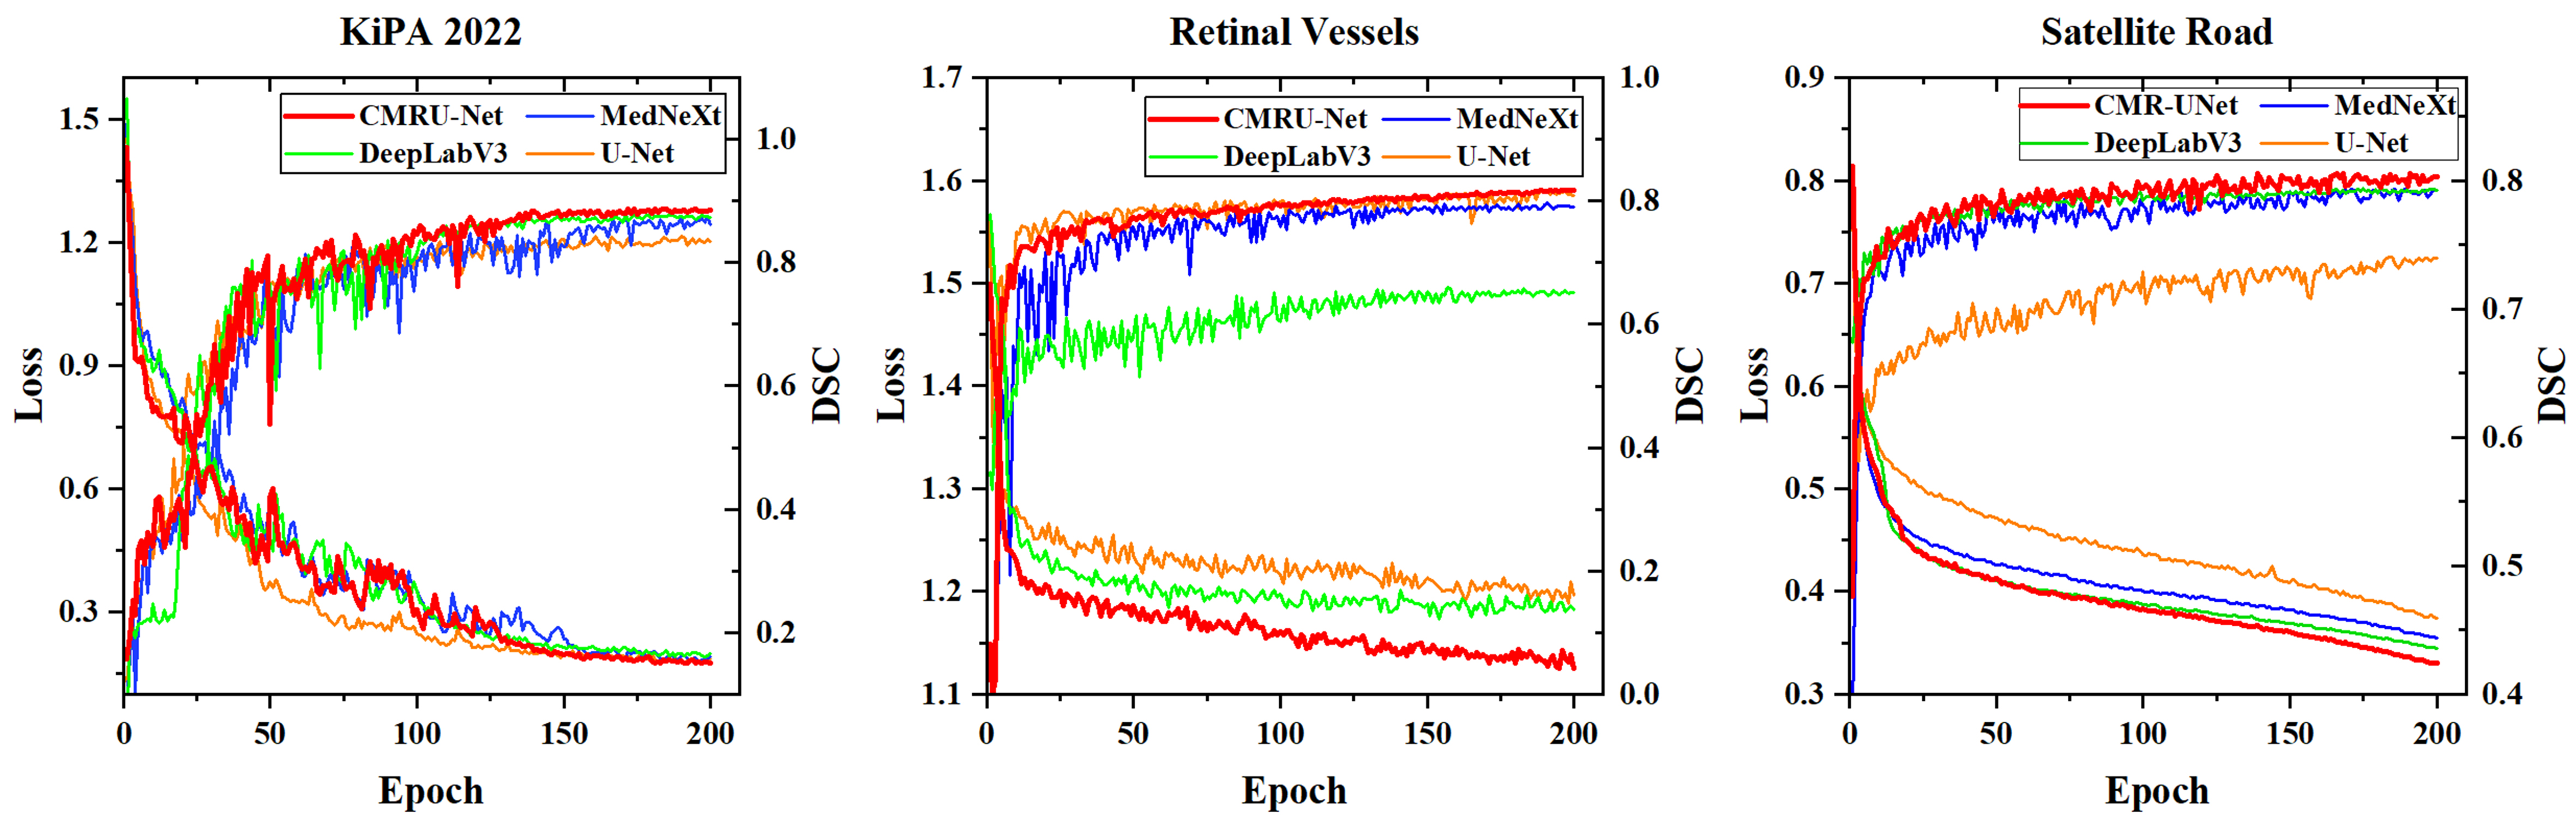

Before conducting numerical analysis, we first plot the loss curves and validation set DSC of CMR U-Net and other networks, as shown in Figure 8. It is not difficult to find that DeepLab V3 in retinal vessels segmentation tasks and U-Net in satellite road segmentation tasks achieved poor training results, while our CMR U-Net has achieved better training results compared to others.

Due to the small size of the KiPA 2022 medical image segmentation dataset, we can clearly see the advantages of CMR U-Net on the satellite road map dataset and retinal vessels dataset. In addition, due to the introduction and continuous increase of contour loss, we observed some shaking in the curve during the training process, but it gradually stabilized in the later stage.